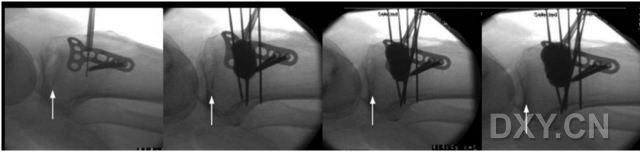

患者取仰卧位,患肢抬高,膝关节屈曲 45 度,在全麻下检查膝关节的稳定性,确保没有韧带结构的损伤。在胫骨前外侧近端作一切口,并在切口的近端作一小的膝关节横行切口,确保手术抬高塌陷的胫骨平台过程可以通过关节腔观察到膝关节胫骨平台的表面。然后利用微创化的手术技术在手术切口部位放置一锁定 T 型支撑钢板,在钢板最下方软圆型螺钉孔内预先置入一枚皮质骨螺钉临时固定钢板,在球囊扩张时可以作为外部皮质的支撑结构,预防皮质破裂,而临时固定的皮质骨螺钉允许后期根据需要调整钢板高度,并在骨折塌陷平台部位的下方前后侧置入两枚克氏针作为遮挡(图 1),为后续手术步骤作准备。

图 1:复位过程的侧位片。A,在胫骨平台塌陷部位置入可扩张球囊进行平台复位。注意在压缩平台的外侧临时固定的钢板,可以在球囊扩张时预防外侧皮质断裂。在骨质压缩区域下方置入 2 枚如图所示位置的克氏针,预防向下扩张。B,在扩张时上述装置可以作为支撑结构使得扩张球囊朝指定方向扩张。

后根据骨折的 X 片选择合适的球囊进针角度,可选择手术切口或者直接在皮肤上穿刺,通过 X 线引导将球囊放置在平台塌陷的中心位置。后续过程和椎体成型术类似(图 2)。